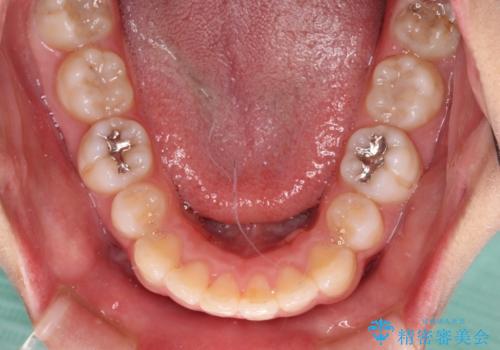

- 下顎前歯を中心に、以前行った矯正治療の後戻りが気になるとのことで来院された患者様です。

後戻りは軽度であったため、インビザライン・ライトにて治療を行うこととしました。